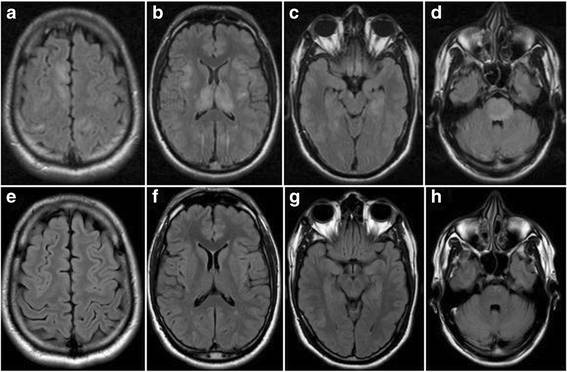

31岁印度男性,既往体健,因意识水平改变至急诊。神经系统症状起病前5天患者有轻微发热(<38°C),咽喉疼痛和头痛。患者近来在印度居留2月。神经系统查体提示步态不稳,呈宽基状,意识水平下降。可见弥漫丘疹和黏膜疹,数天后自发消失。红细胞、白细胞(13.000/μL)、血沉(30mm/h)和C反应蛋白(48mg/l)轻度升高。因考虑感染性脑炎,患者起初接受阿昔洛韦和头孢曲松治疗。脑脊液检测提示总蛋白水平53mg/dl,细胞数179/μL(90%单核细胞),未见寡克隆IgG条带。头颅磁共振FLAIR和T2WI可见丘脑、基底节、内囊、颞叶内侧面和脑干弥漫高信号伴皮质下、脑室旁和皮质区高信号小病灶不伴强化(图a-d)。DWI上病灶轻度弥散受限。全脊髓MRI正常。

(图:a-d:发病时的FLAIR;e-h:治疗后复查的FLAIR;可见皮质和皮质下病灶伴双侧丘脑和内囊,颞叶内侧面和脑桥受累,无明显强化;免疫球蛋白治疗后皮质,丘脑和基底节病灶几乎完全消失,颞叶和脑干病灶较前好转)

常见病毒和不典型感染PCR检测均为阴性。细菌和真菌培养无殊。自身免疫性脑炎相关抗体、副肿瘤相关抗体、抗核抗体全套、甲状腺功能及抗体全套均阴性。结缔组织疾病,血管炎,白塞病以及桥本脑病等的诊断标准尚未达到。血清(滴度1:5120)和脑脊液(滴度1:8)抗髓鞘少突胶质细胞糖蛋白(MOG)抗体阳性。患者接受静脉注射免疫球蛋白治疗5天,症状较前明显改善。2周后复查MRI,原病灶基本消失(图e-h)。仅遗留轻度的步态不稳。